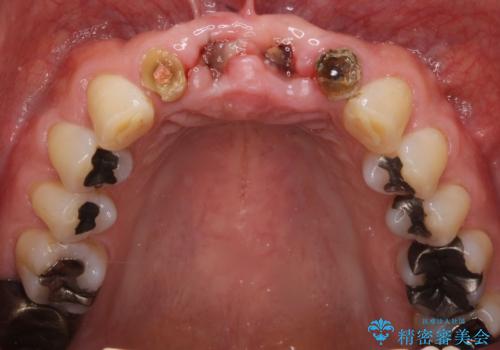

- お風呂場で転んで上の前歯が2本抜けてしまったことを主訴に来院された患者様です。

精査したところ、左上の側切歯(左上2)も破折しており保存不可能な状態でした。

左上の側切歯(左上2)を抜去し、右上の側切歯(右上2)の再根管治療後、セラミックのブリッジによる補綴を行いました。